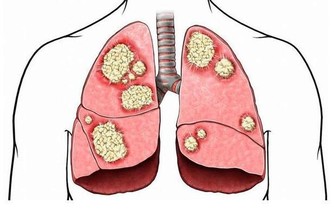

在許多前列腺癌病人中,病灶轉移很常見,大約有三分一的病人在初次就醫時就已有淋巴結轉移,多發生在骼內、骼外、腰部、腹股溝等部位。可引起相應部位的淋巴結腫大及下肢腫脹。血行轉移多見於骨骼,如骨盆、骶骨等,或內臟,如肺、肝、腦等。(參考網站:聞康男性)